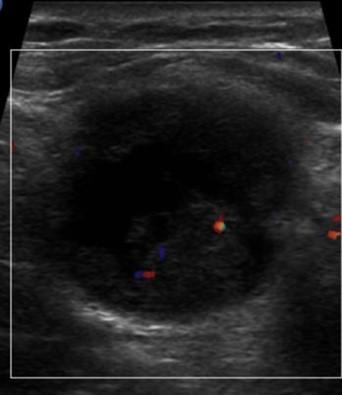

Ung thư vú

Ung thư vú - Ảnh 4

Ung thư vú - Ảnh 5

» Thông tin: Nữ giới – 57 tuổi.

» Lâm sàng: Khối tuyến vú.